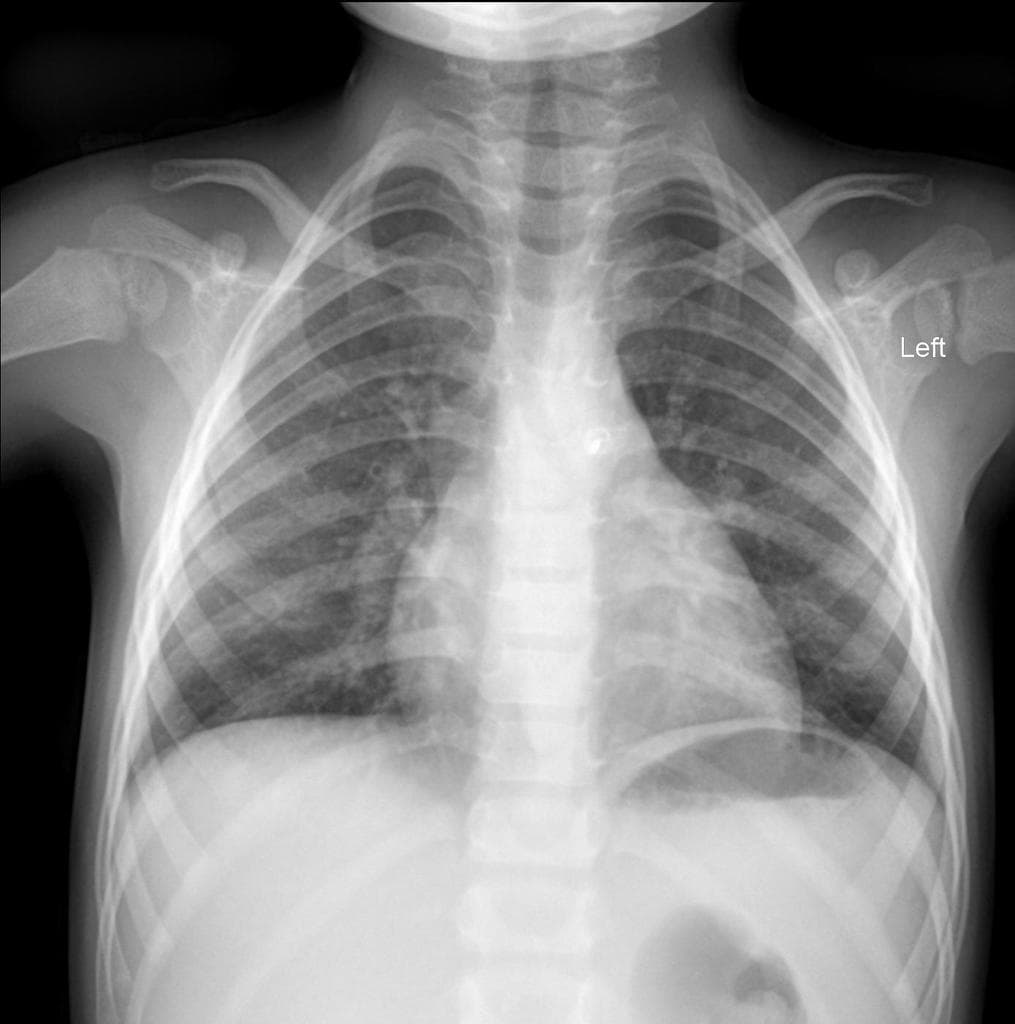

Chụp cắt lớp vi tính mạch máu động mạch chủ ngực (CT Angiogram Thoracic Aorta):

Chụp có cản quang pha động mạch (sử dụng Omnipaque 350). Không có hình ảnh cắt lớp trước đây để so sánh.

Không thấy tổn thương động mạch chủ do chấn thương hoặc máu tụ trung thất. Ghi nhận thấy ống động mạch còn thông (patent ductus arteriosus).

Tim phải và động mạch phổi không giãn.

Ghi nhận tổ chức tuyến ức còn sót (remnant thymic tissue).

Không có hạch rốn phổi, hạch trung thất hoặc hạch nách to.

Phổi trong sáng, không đông đặc, không xẹp phổi, không nốt hoặc khối phổi.

Không tràn khí màng phổi hoặc tràn dịch màng phổi.

Nhiều ổ khí và hình ảnh tăng đậm đặc/xơ hóa liên quan ở mô mềm vùng trước giữa thân xương đòn trái, phù hợp với chấn thương mô mềm.

Không thấy gãy xương dưới vùng được chụp của xương đòn trái.

Không gãy xương cột sống ngực, xương sườn hoặc xương ức.